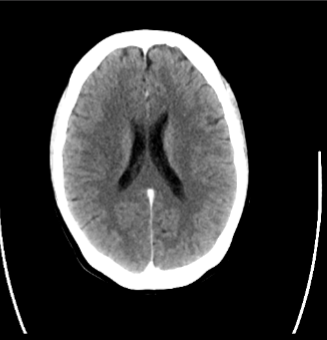

CT can be done to evaluate for cerebrovascular disease, specifically, to evaluate for the presence or absence of what 5 pathologies?

Cerebral infarctions

Hemorrhage

Tumors

Masses

Anatomic variations

What imaging modality is seen here?

CT/CTA